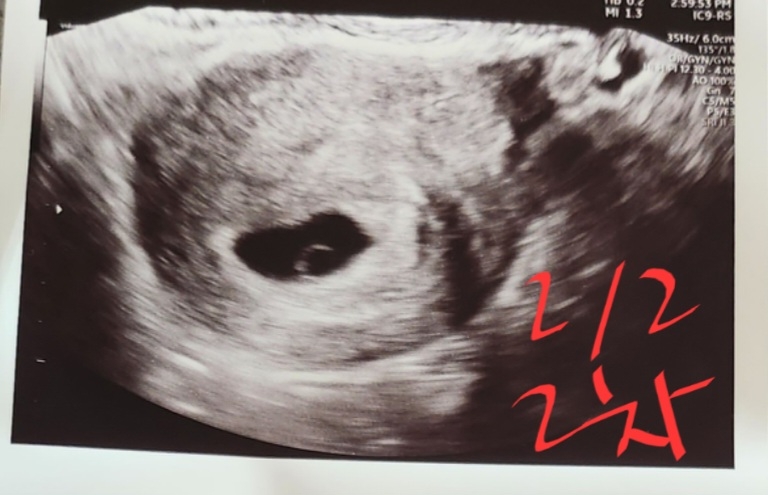

6주초음파ㅠㅠ

5주추정(1/19일)에 1차촘파로 아기집확인하고, 2주후 7주추정(2/2일)에 2차촘파보러갔는데 아가는 안보이고 난황만보인다고하셨어요.. 7주추정이아니라 6주정도인것같다고하시면서 일주뒤에는 아가가 안보이면 안된다고, 아직 기회가있다고 하셨는데 저 기회가있단말이 너무 불안해요ㅠㅠ 유튜브찾아보니 아가집확인하고 2주후에는 아가랑 심장소리를 꼭들어야한다던데..저같은분계신가요..?? 아가 이상없을까요..??